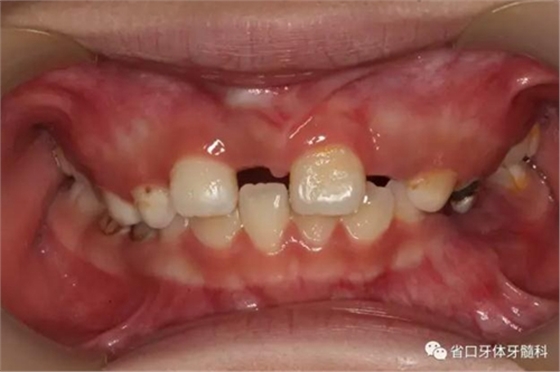

檢查:替牙列,12、21已萌出,11、22未萌,12、21間隙約5mm,右上前牙區(qū)前庭溝處見黏膜隆起,11牙冠未破齦。

口內(nèi)情況:正面觀